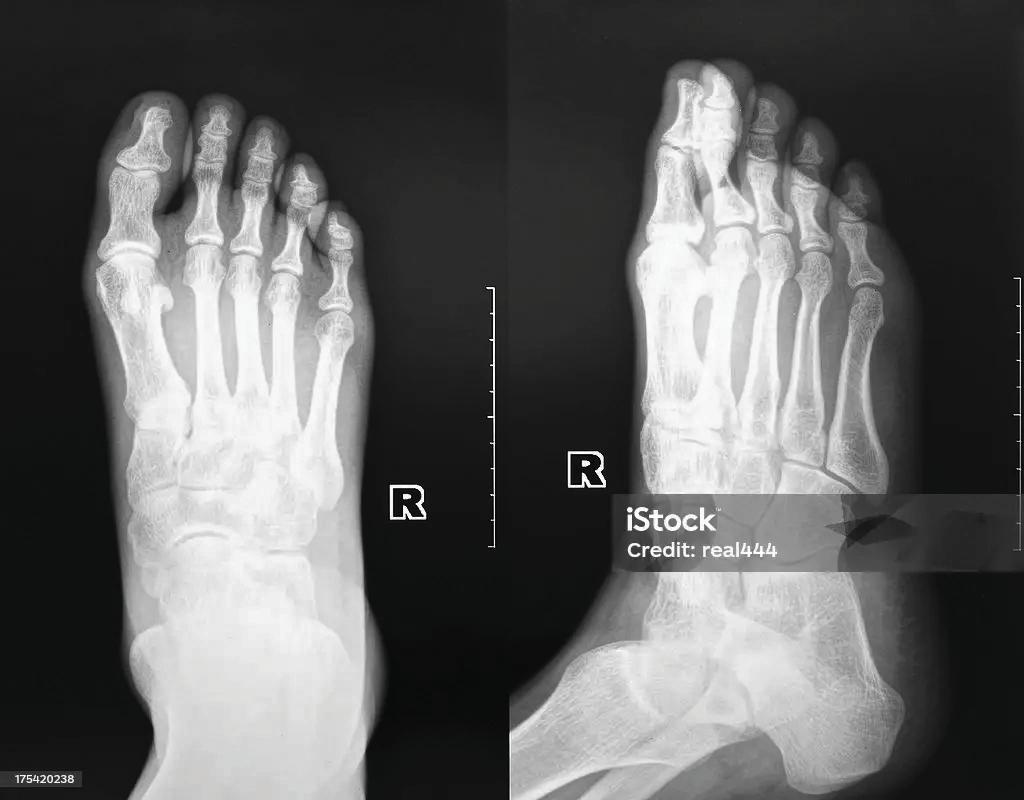

Sault Area Hospital deploys innovative HIFU system for chronic pain

Sault Area Hospital (SAH) has become the first hospital to integrate the Neurolyser XR High-Intensity Focused Ultrasound (HIFU) system into a clinical setting, marking a significant milestone in chronic pain management and hospital-based innovation.

This initiative reflects SAH’s leadership in redesigning care for underserved populations and advancing clinical practice through technology.

The Neurolyser XR HIFU system utilizes focused ultrasound energy to thermally ablate targeted peripheral nerves responsible for transmitting pain signals. The procedure is performed under precise imaging guidance, combining X-ray and optical navigation to ensure accurate localization of the treatment site.

Ultrasound beams are converged through intact skin – similar to the focal point created by a magnifying glass – delivering therapeutic heat to the nerve tissue without the need for needles, incisions or radiation exposure.

One of the most compelling clinical benefits is the rapid onset of pain relief, with some patients reporting significant improvement within 30 minutes posttreatment.

Additionally, the short recovery time allows most individuals to resume daily activities the same day.

The Neurolyser XR HIFU system also facilitates timely evaluation of treatment efficacy; if no relief is observed within seven days, clinicians can promptly adjust the pain management strategy.

This technology also improves safety by reducing radiation exposure during treat-

ment, making it a more accessible and effective option for a wider range of patients.

SAH’s adoption of the Neurolyser XR HIFU system underscores its commitment to expanding access to advanced care and driving innovation in hospital-based pain management.

This transformative technology was championed by locum physicians Dr. Kevin Smith and Dr. Michael Gofeld, whose clinical experience with the Neurolyser XR HIFU system in private practice since January 2025 demonstrated its effectiveness.

The method was introduced in Canada by Dr. Smith and Dr. Gofeld, who conducted pivotal studies that led to Health Canada’s approval of the treatment.

Their research included both preclinical and clinical trials, which confirmed the superb safety profile of the Neurolyser XR

HIFU system and demonstrated its superior effectiveness compared to traditional radiofrequency ablation (RFA).

Their advocacy through SAH’s Physician Recruitment and Retention program was instrumental in acquiring the system, with additional support from the Sault Area Hospital Foundation, making it possible to integrate this technology into a hospital setting for the first time worldwide.

“This is a proud moment – being able to offer a novel, non-invasive treatment to a greatly underserviced community is deeply meaningful,” said Dr. Smith. “In my line of work, treatment typically involves needles and invasive procedures that require healing and recovery. Now, with the Neurolyser XR HIFU system, we’re able to achieve the same, if not better, patient out-

comes without those burdens. This is a transformative step forward, setting a new standard for how we treat chronic pain conditions in a hospital setting.”

For his part, Dr. Gofeld said: “Many of the patients we see with chronic spinal arthritis are older adults who face significant limitations in their daily lives due to persistent pain. This new treatment option is non-invasive, offers extended relief, and helps patients return to a more active lifestyle without the burden of long recovery times. It’s a meaningful advancement in how we support comfort and mobility for this population.”